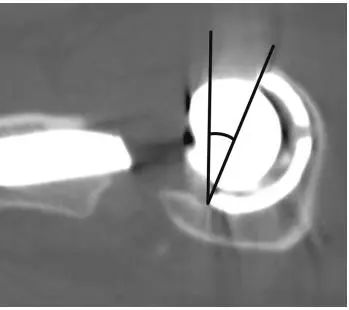

下图为CT测量前倾角(图8)

(图8)